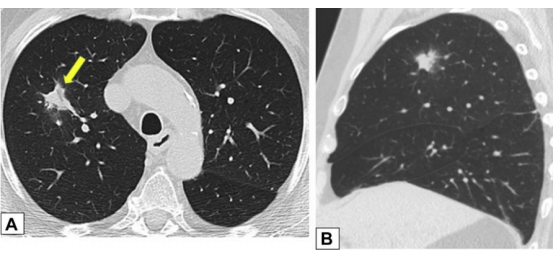

实变是OP病例中最常见的发现,发生于近75%的病例中,病变通常在双基底、支气管血管周围和/或外周。图1A为一名女性患者,右肺上叶周围实变,其曾因乳腺癌接受过放射治疗,并经活检证实为OP。图1B患者左肺下叶和舌叶周围实变,活检证实为继发于淋巴瘤化疗的OP。

图源:Chest, 2022, 162(1):156-178.